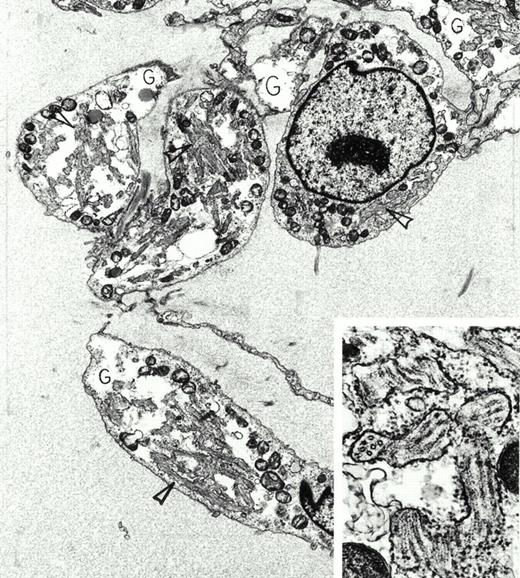

Extraskeletal myxoid chondrosarcoma. A 72-year-old asymptomatic man was found to have a large mass in the thigh by physical examination. This was removed surgically, and radiation therapy was administered to the area. Despite multiple bilateral, slowly enlarging pulmonary metastases, he remained in good health 4 years later. Immunoperoxidase stains of the tumor were positive for vimentin and negative for actin, desmin, myoglobin, S-100 protein, keratin, and epithelial membrane antigen. By electron microscopy, the tumor was composed of interconnected chains of plump polygonal and elongate spindle cells in an abundant edematous matrix. Tumor cells were focally invested in basal lamina, displayed large, electron-lucent, cytoplasmic glycogen pools (G) and extensive enlarged cisterns of rough endoplasmic reticulum packed full with tubules (arrowheads). This tubular array is seen at higher magnification and in both longitudinal and cross-sectional views in the inset. Original magnification ×8,000 (inset, ×59,000). (Courtesy of Ann M. Dvorak, MD, Department of Pathology, Beth Israel Deaconess Medical Center, 330 Brookline Ave, Boston, MA 02215.) {/ANNT;80256n;;center;0n}